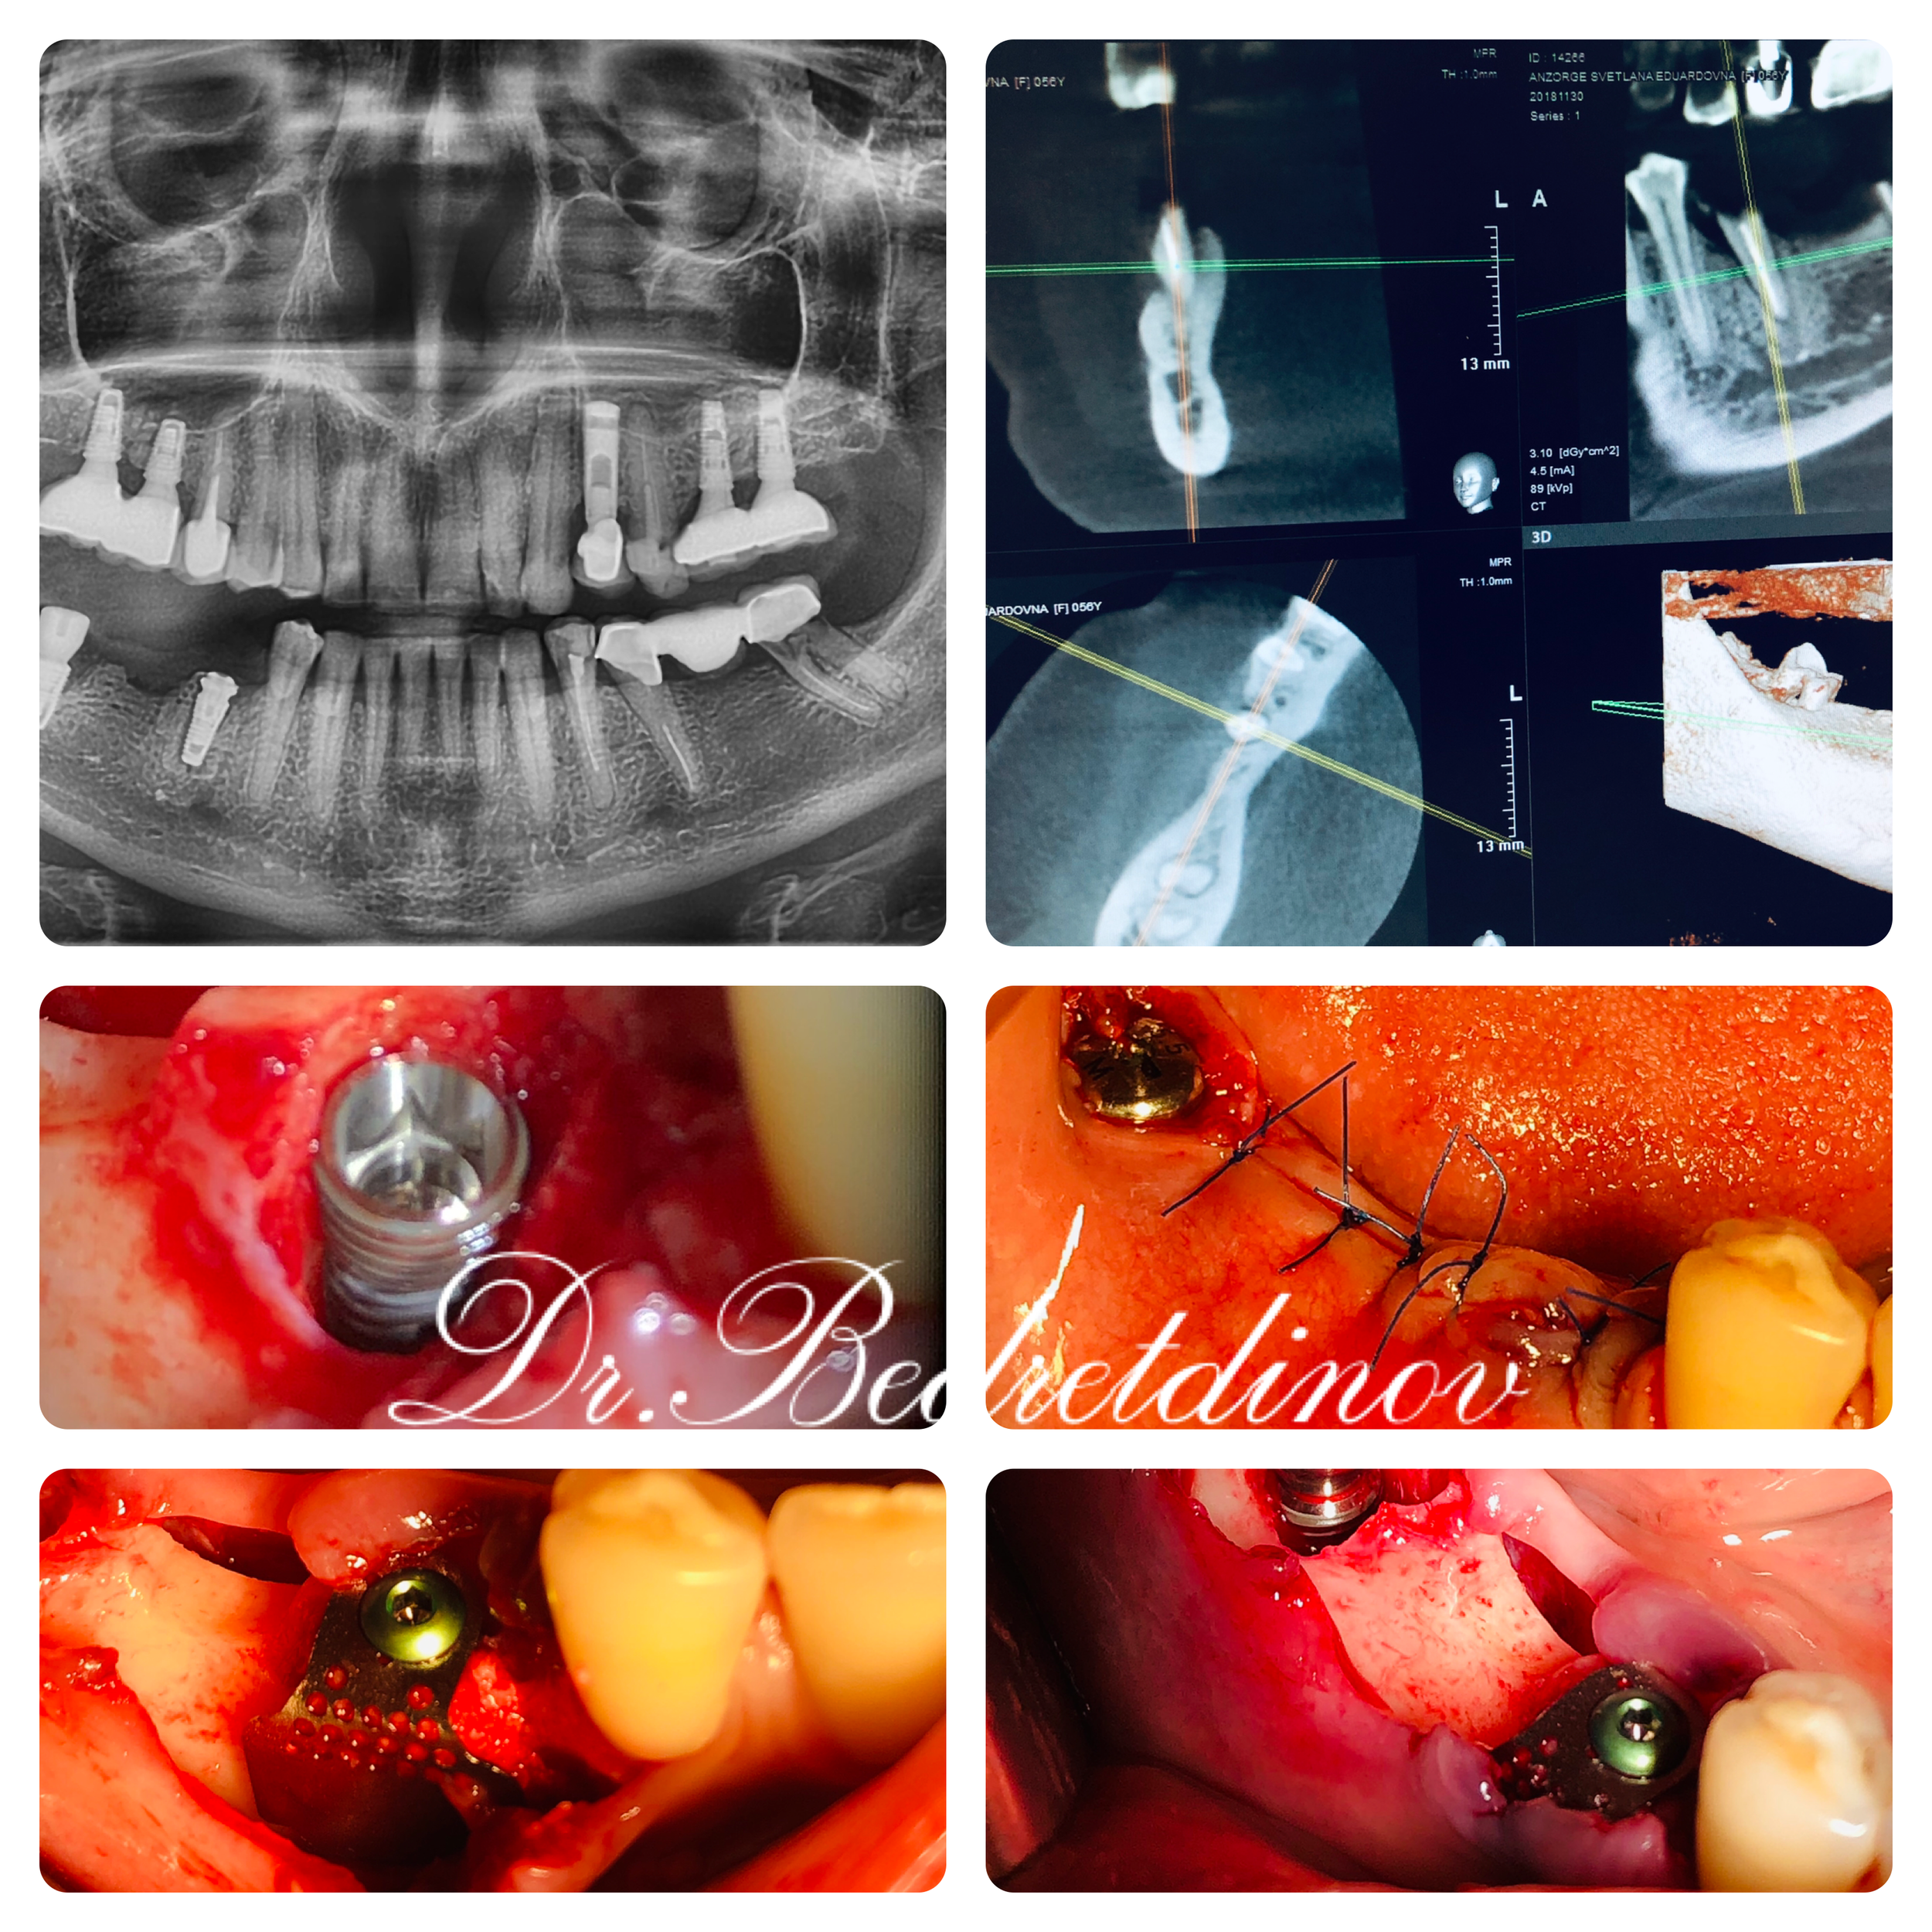

Вживление импланта Удаление зубов 4.5,4.7 с одномоментной дентальной имплантацией с фиксацией титановой сетки JEIL в области 45 Featured Почему болит зуб? Как выбрать клинику стоматологии? All-on-8: Полное протезирование на 8 имплантах Удаление "восьмерок": от классики до ультразвука и под наркозом Как стоматологи обманывают пациентов Скрытый враг вашей улыбки: Как обнаружить кариес, пока не стало слишком поздно VIVI.clinicJanuary 10, 2019до_после